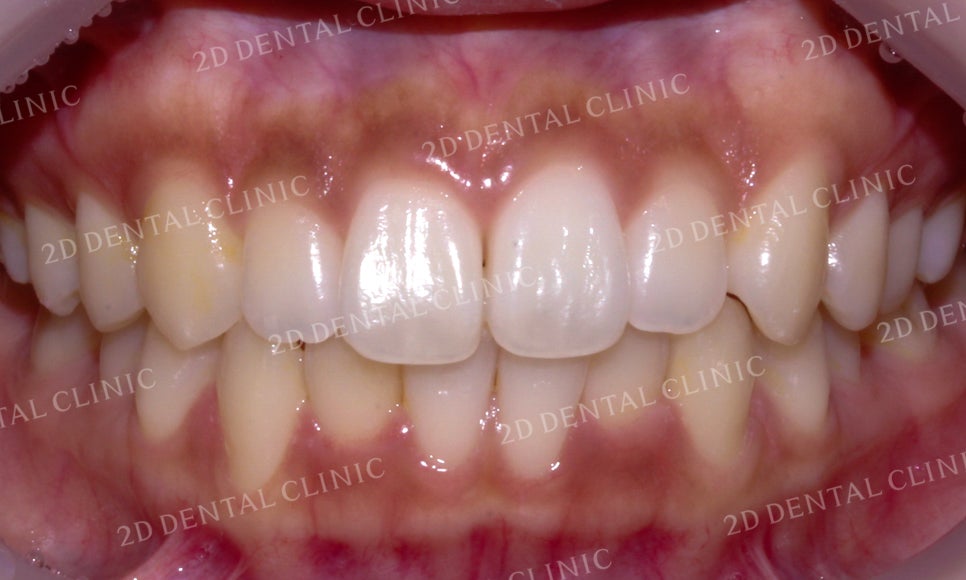

전치부의 모습을 보시면

치열이 삐뚤거리고 하악에서

미세한 치은 퇴축이 발견되었는데요,

교정 후 전치부의 치열이 고르게 바뀌고

내려앉았던 하악의 잇몸이

비교적 수복된 모습입니다.

*환자분의 경우 부분교정을 선택하셨기 때문에

상하악의 정중선이 완벽하게 맞지 않을 수 있습니다.

이 점 참고하시어 포스팅을 읽어주세요 : )